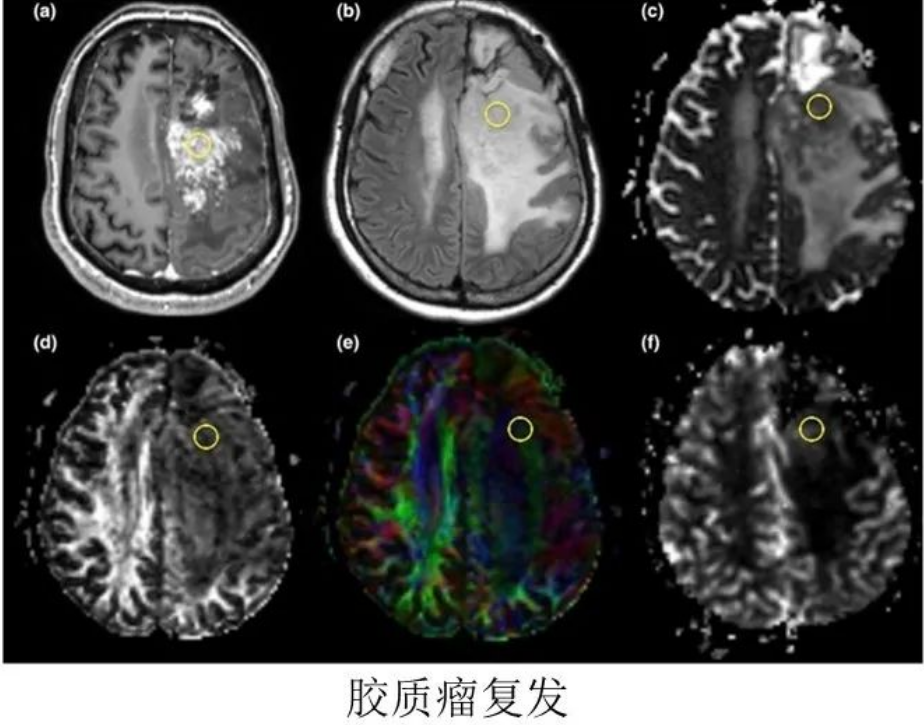

1.磁共振增强:放化疗后可导致血管内皮细胞损伤、坏死,造成血管内皮细胞紧密连接损害,BBB功能损害、通透性增强,在MR增强强化。MR增强上出现强化灶、新强化灶。类似肿瘤复发的影像学表现。胶质母细胞瘤放疗后,MR增强强化见于:70%:肿瘤复发、坏死(结节或多发强化区,术后3月后);30%:单侧放射性坏死(地图样强化)。

肿瘤复发:多发病灶沿白质纤维束播散、累及胼胝体